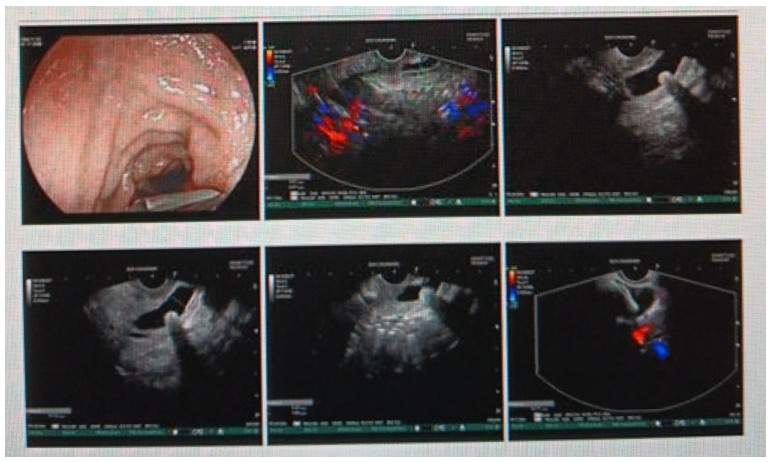

消化內(nèi)科肝病亞??茍F隊詳細討論,分析患者情況后,取消了周女士的肝穿刺活檢檢查,建議患者先行超聲胃鏡下膽胰掃查。在內(nèi)鏡醫(yī)師第三只眼——超聲胃鏡的掃查下,發(fā)現(xiàn)引起周女士肝功能受損的罪魁禍首原來是膽總管末端結石!伍友興主任醫(yī)師帶領團隊給予患者行ERCP下取石后,周女士未再出現(xiàn)腹痛,肝功能恢復正常。

無獨有偶,劉先生也為反復出現(xiàn)肝功能受損到多家醫(yī)院就診檢查,未能找到原因,來到衡陽市中心醫(yī)院消化內(nèi)科就診,希望能在肝穿刺活檢下得出病因。在行肝穿刺活檢之前,醫(yī)生建議劉先生行超聲胃鏡膽胰掃查,發(fā)現(xiàn)引起劉先生反復肝功能受損原因,亦是膽總管結石引起,在ERCP術取石術后,患者肝功能恢復正常,未再出現(xiàn)異常情況。

張丹霞主任醫(yī)師介紹,超聲內(nèi)鏡通過胃十二指腸自然腔道,可以將探頭貼近相應的位置,近距離的觀察胰腺及膽道系統(tǒng),準確捕捉到直徑小于5毫米的胰腺異常病灶及膽道系統(tǒng)病灶。而體表B超常受皮膚、脂肪或腸道氣體干擾。CT或磁共振檢查只能提供靜態(tài)圖像,且對膽胰管陰性結石或是未引起明顯膽管梗阻性的結石檢查有局限性,因此對于有輕微腹痛合并肝功能受損的患者,建議常規(guī)行超聲胃鏡下膽胰掃查。超聲胃鏡、腹部彩超、腹部CT、腹部MRI同為診斷膽管細微病變的四架馬車,在膽總管結石診斷方面,超聲胃鏡膽胰掃查同ERCP一樣,是敏感性高、特異性強的診斷方法。超聲胃鏡發(fā)現(xiàn)可疑病變,可以完成穿刺活檢,還可行囊腫穿刺引流、膽管減壓、消融術等。